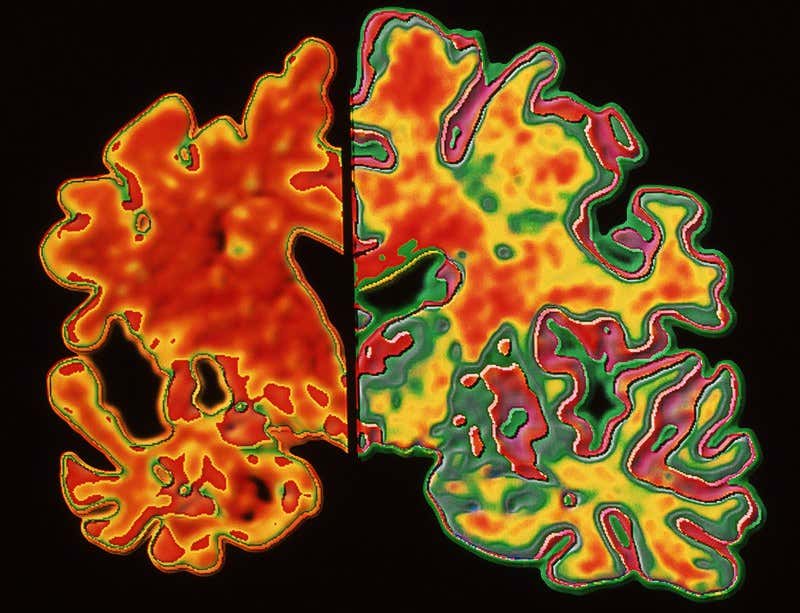

The death of nerve cells makes the brains of people with Alzheimer’s disease (left) smaller than those of people showing no signs of dementia (right) (Image: Pasieka/Science Photo Library)

Globally, 35 million people are living with Alzheimer’s. It is characterised by a toxic build up of amyloid and tau proteins in the brain, which destroys the neurons. Several blood tests can diagnose the disease, but until now, none has had the sensitivity to predict its onset.